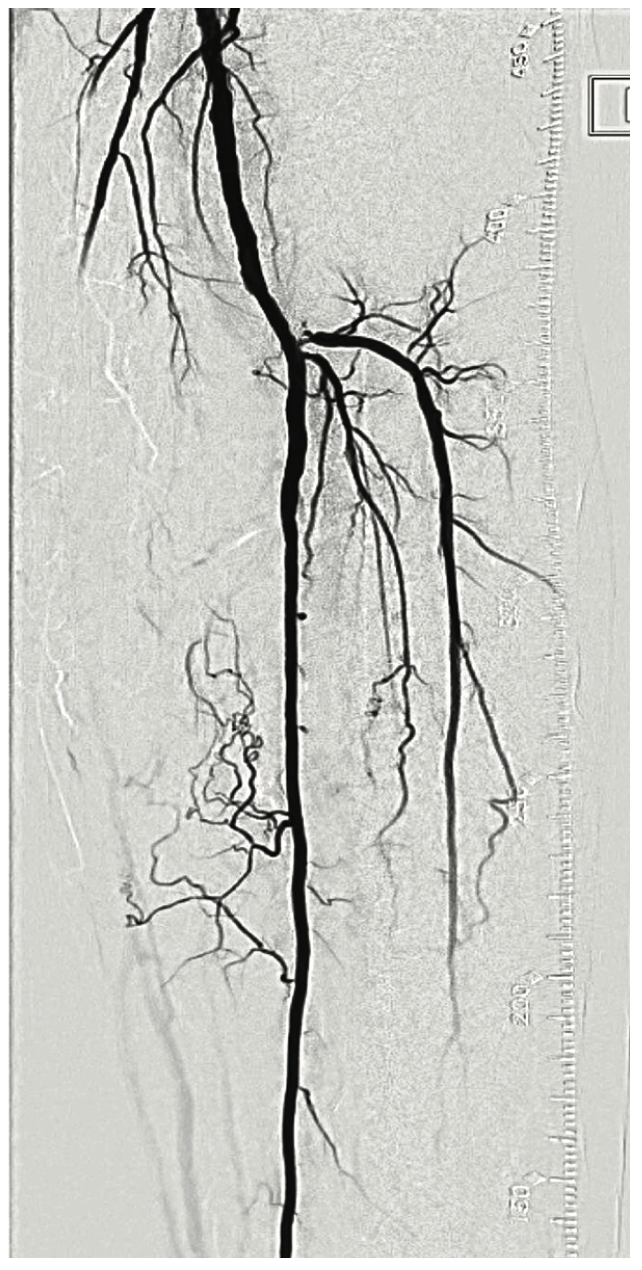

This is a 67-year-old male with past medical history significant for diabetes, hypertension and advanced chronic kidney disease (Stage IV). The patient presented with a non-healing ulcer involving the left great toe. The patient was evaluated by podiatry who examined the patient and determined that the arterial flow was impaired. Office ankle-brachial index (ABI) was deemed to be not helpful with non-compressible values. A detailed diagnostic angiogram revealed evidence of an occluded posterior tibial artery (PT) with an occluded dorsalis pedis artery (DP). Visualization of the plantar circulation was limited secondary to a poor collateral system (Figure 2).

Interestingly, the DP across the ankle joint had what appeared to be a “White Stop Sign”. We have provided an image of the DP under ultrasound and fluoroscopy (Figure 6). The White Stop Sign is a term we use to describe a vessel that is completely opacified with calcified plaque and occupies a long segment of the vessel, making it difficult to cross. In this case, we were able to achieve partial pedal loop reconstruction. This ultimately allowed blood flow to the inferior digital branch, achieving adequate angiosome revascularization (Figures 7-8).